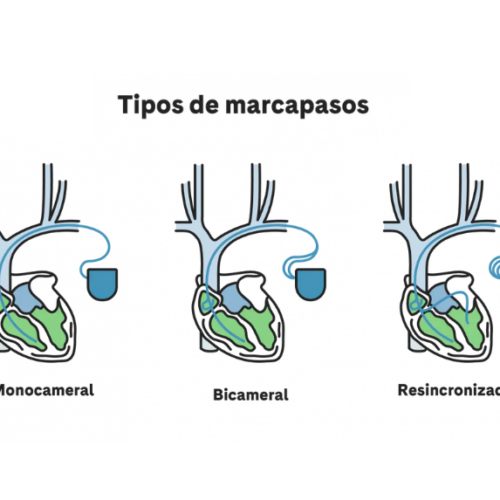

Tipos de marcapasos y su cuidado

El uso de marcapasos en el tratamiento de problemas cardiovasculares y hay diversos tipos, especializados según la afección que se quiera resolver.

Marcapasos en el tratamiento del bloqueo atrioventricular

El marcapasos es una de las opciones de tratamiento eficaz y definitiva para el bloqueo atrioventricular, sobre todo en los casos donde peligra la vida del paciente y las regulaciones farmacológicas no logran los resultados esperados.